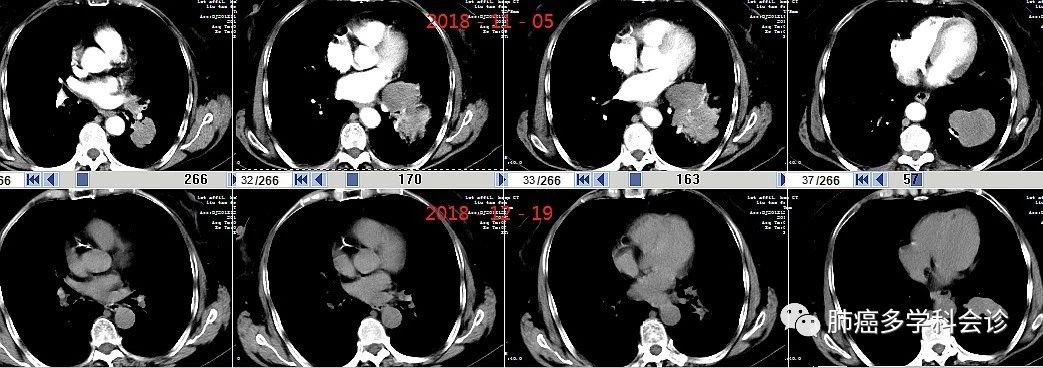

服药1周后咳嗽明显减轻,1月余后返院复查,肿块明显缩小:3.jpg上排2018-11-05,下排2018-12-19